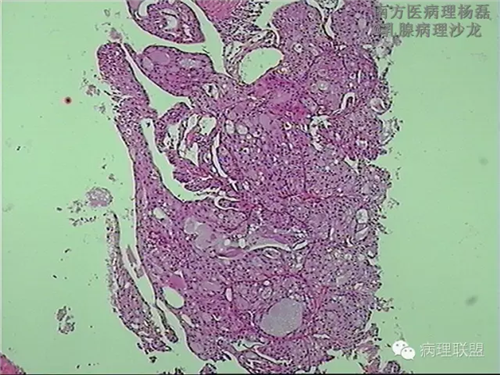

肺转移性乳腺分泌性癌?-病例讨论

女,51,右肺多发结节穿刺。15年前行右乳肿物切除,具体不详。